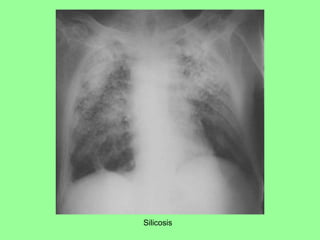

Silicosis

• #27 This chest radiograph demonstrates so many silicotic nodules that they have become confluent areas of silicotic nodules that have resulted in severe restrictive lung disease. This patient became severely dyspneic.

• #28 This chest radiograph demonstrates so many silicotic nodules that they have become confluent areas of silicotic nodules that have resulted in severe restrictive lung disease. This patient became severely dyspneic.